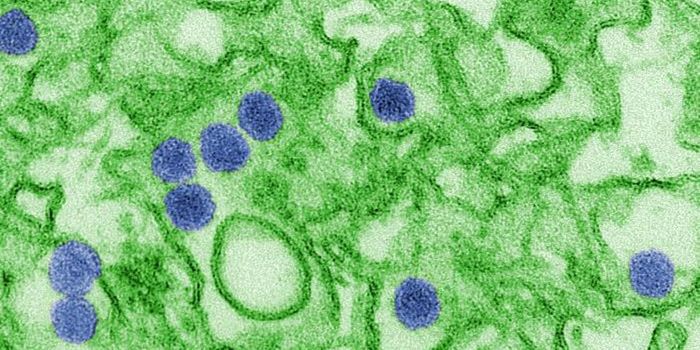

SEP 20, 2021Genetics & GenomicsHuman immunodeficiency virus (HIV) is a retrovirus, which is a type of virus that can write its genetic material into th ...